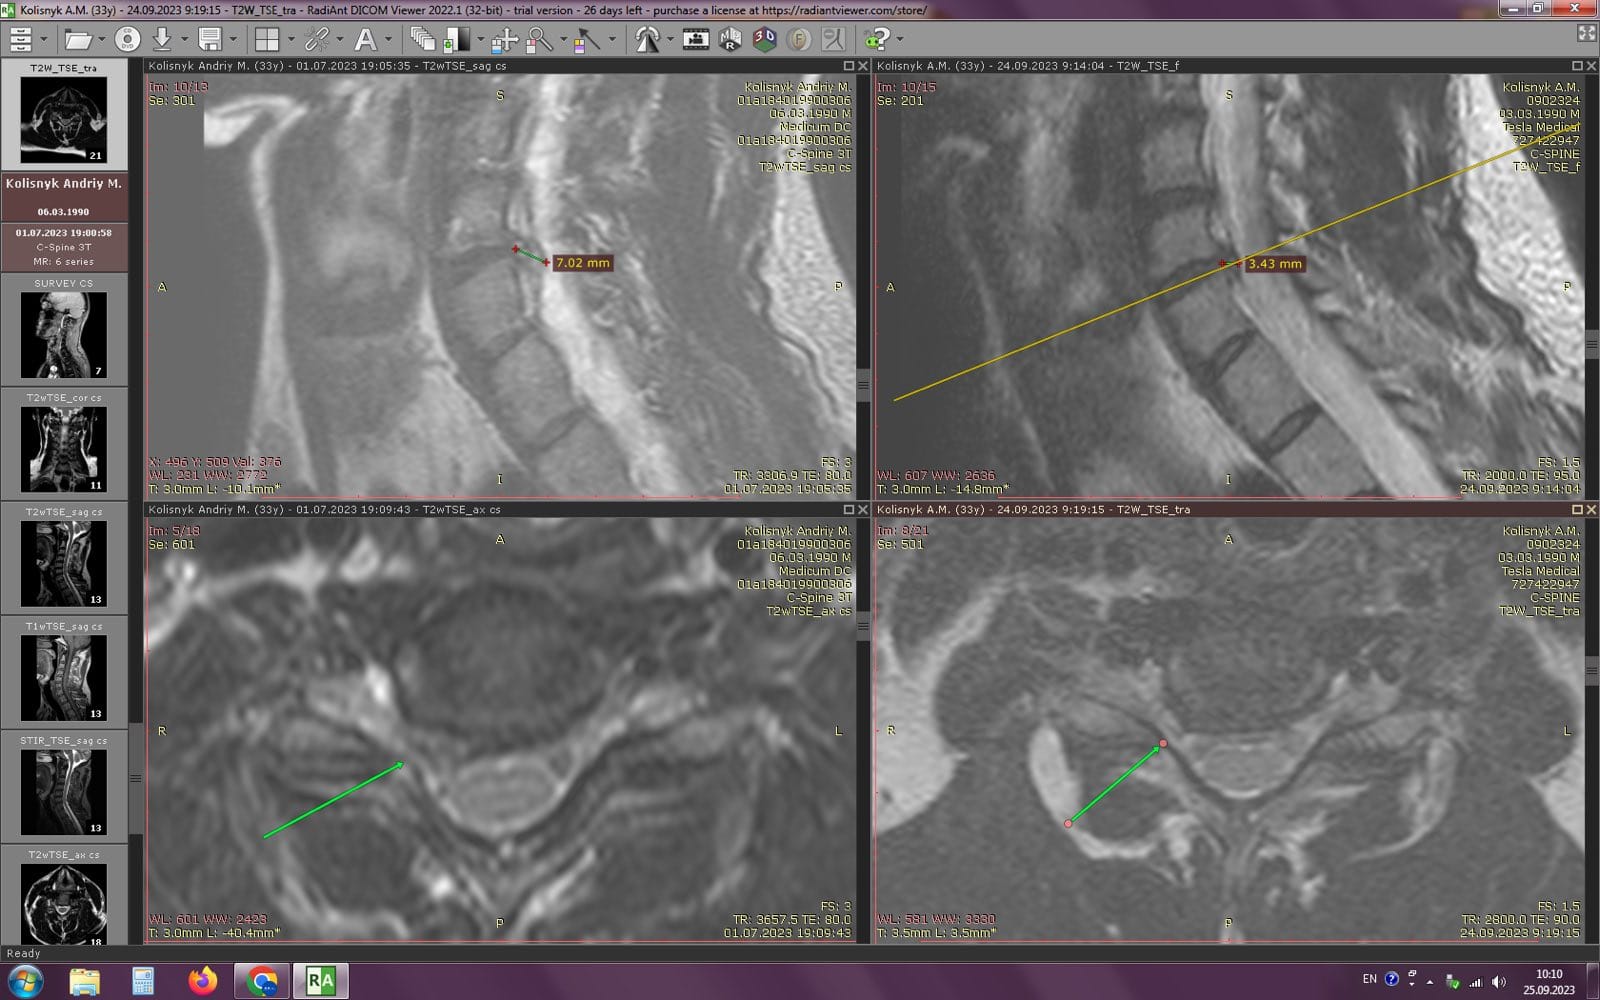

Метод лікування грижі шляхом стимуляції резорбції в Україні був впроваджений у 2020-2021 роках.  Алгоритм оцінки грижі на предмет резорбції, що використовується у клініках – є авторським, розроблений лікарем Боханом А.Ю.